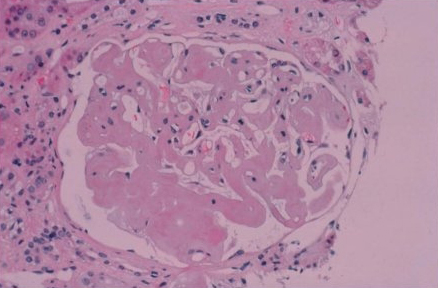

Os depósitos de amiloide são sempre extracelulares e parecem amorfos.[Figure caption and citation for the preceding image starts]: Vaso sanguíneo com coloração vermelho Congo em biópsia da medula óssea demonstrando birrefringência verde patognomônica de amiloidoseMorie A. Gertz, MD; cortesia da Mayo Clinic [Citation ends].

[Figure caption and citation for the preceding image starts]: Biópsia renal demonstrando depósitos amiloides como substituição amórfica da arquitetura glomerularMorie A. Gertz, MD; cortesia da Mayo Clinic [Citation ends].